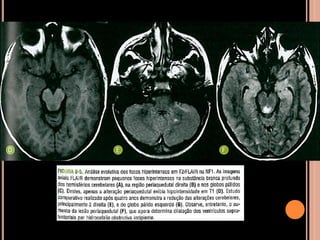

Área de vacuolização de mielina

 Origem é controversa;

 Achado típico em crianças com NF1;

 Focos hiperintensos em T2 e no FLAIR em núcleos

da base, cápsula interna, tronco encefálico e

cerebelo;

 Mais comum no globo pálido, geralmente bilateral;

NF1

Vacuolização de mielina

 Aparecimento geralmente aos 3 anos  aumenta

até os 12 anos  tendência a regredir;

 Raro observar após os 20 anos de idade;